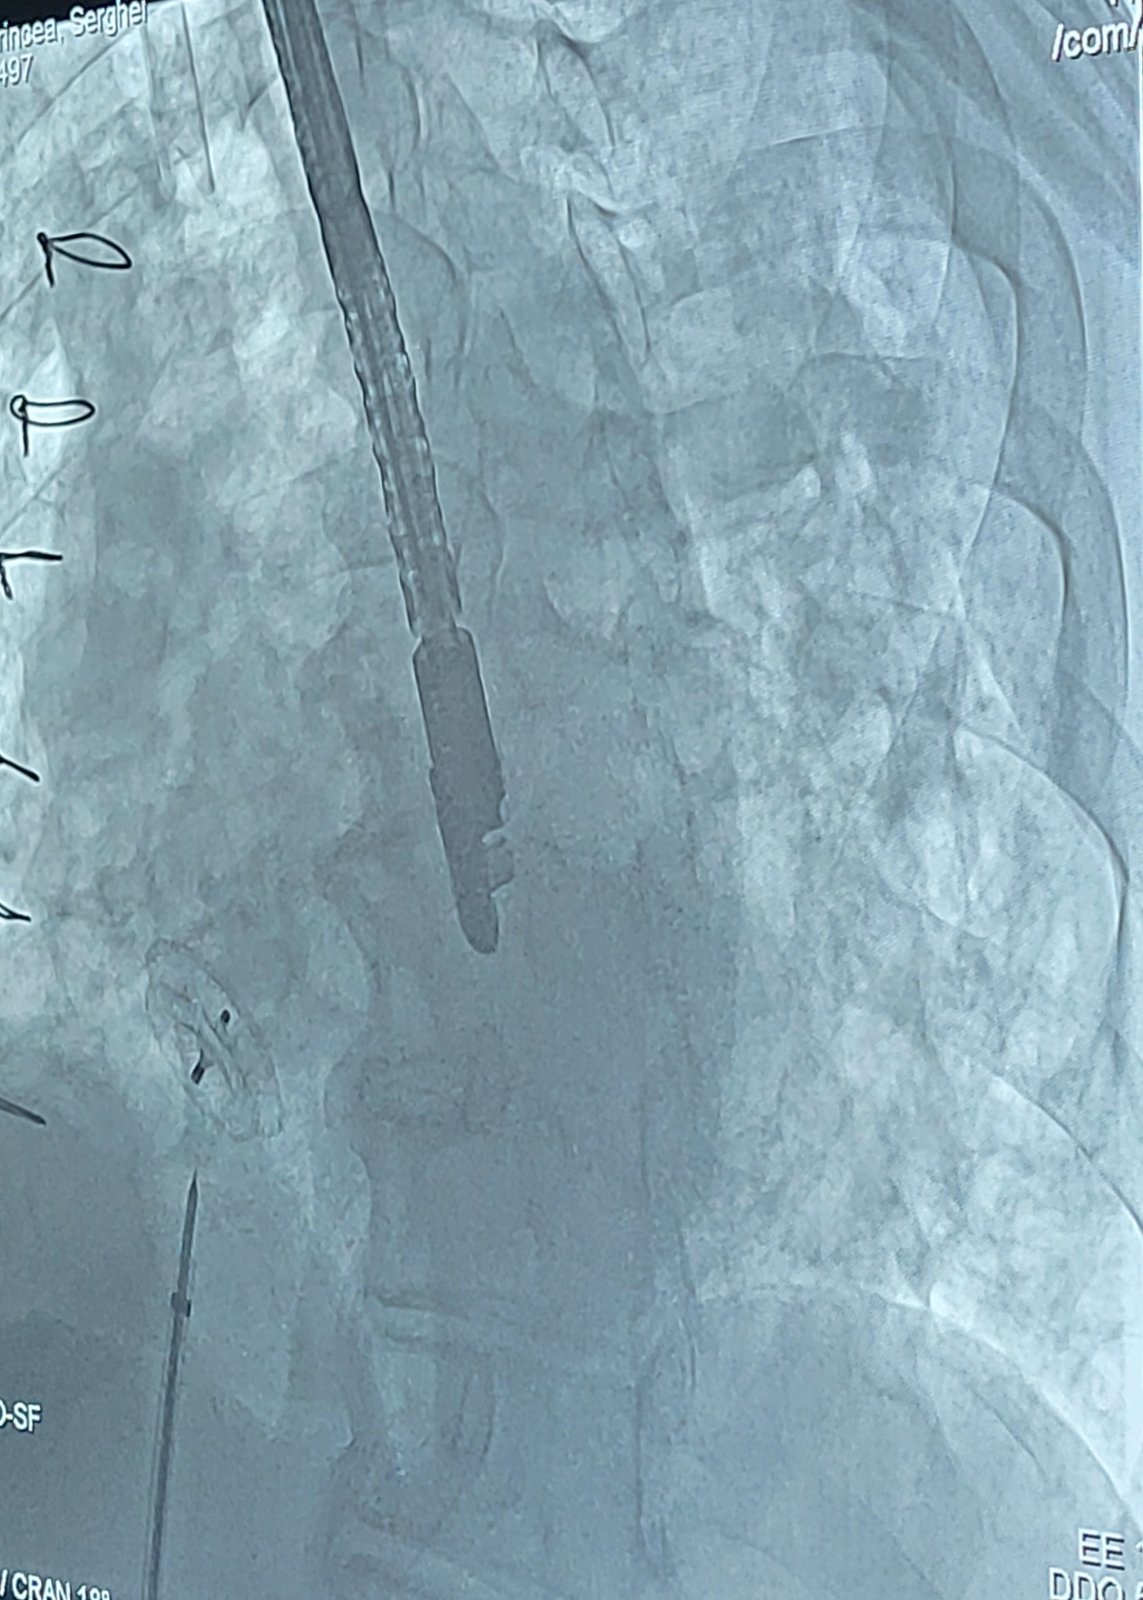

Ocluderul este un dispozitiv asemănător unei umbreluțe. Inițial acesta este pliat, iar după poziționarea lui exactă la locul defectului, umbreluța care prezintă două componente asemănătoare unor discuri atașate în porțiunea centrală se va deschide și va obtura defectul. Procedura este minim-invazivă. Se efectuează sub anestezie generală și poate dura între 60 și 120 de minute.